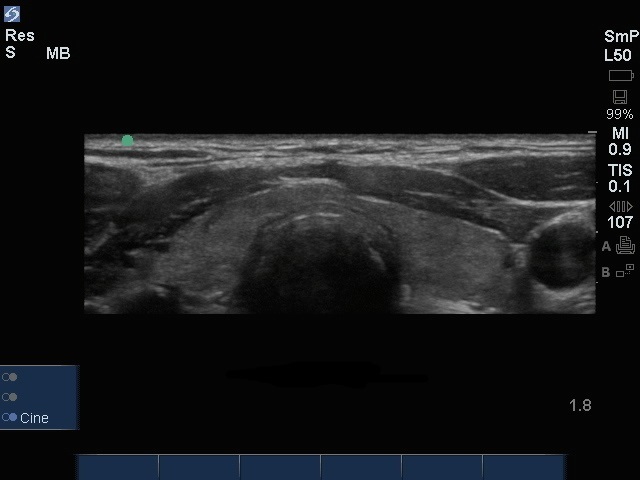

Edge : Image, coupe transverse de la thyroïde